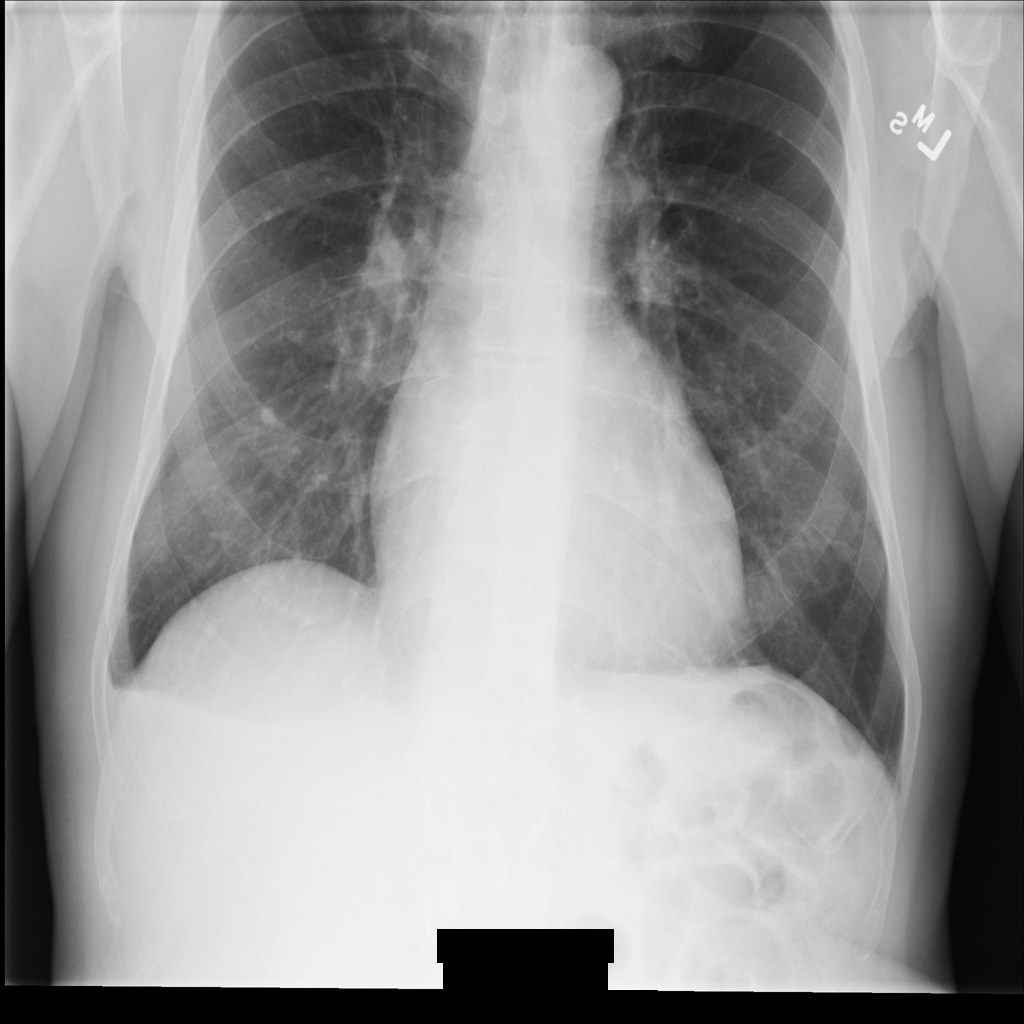

Beispielbild

Einige Beispiele auf dieser Seite enthalten eine Ausgabe des de-identifizierten Bildes. In jedem Beispiel wird das folgende Originalbild als Eingabe verwendet. Sie können das Ausgabebild jedes De-Identifizierungsvorgangs mit diesem Originalbild vergleichen, um die Auswirkungen des Vorgangs zu sehen:

Nach der De-Identifikation des Bildes mit REDACT_SENSITIVE_TEXT_CLEAN_DESCRIPTORS sieht es so aus. Beachten Sie, dass nicht der gesamte eingebrannte Text am unteren Rand des Bildes entfernt wurde. Der Text Female wird weiterhin angezeigt, da PatientSex (0010,0040) nicht zu den Standard-DICOM-infoTypes gehört.

REDACT_SENSITIVE_TEXT_CLEAN_DESCRIPTORS.DICOM-Tags de-identifizieren